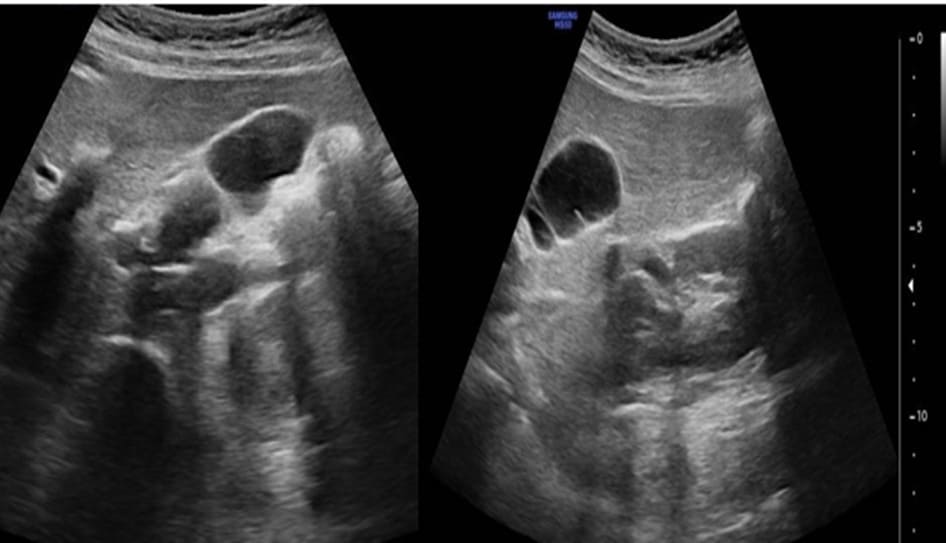

The Abdominal Ultrasound study was requested which showed thickened gall bladder wall of 8 mm and average gallbladder capacity. It also showed a septum of gallbladder at the distal body which divides the gallbladder into two parts. No stones or mud were seen while the caliber of the common bile duct was normal of 3 mm (Figure 1). Findings were discussed with the patient. The patient has agreed with the plan of management of laparoscopic cholecystectomy. The anesthesiologist preoperatively evaluated the patient then he was electively admitted and prepared for the operation. The procedure was uneventful laparoscopic cholecystectomy in which the initial laparoscopic assessment showed no signs of inflammation with clear anatomy of cystic duct and cystic artery.

Figure 1: Abdominal Ultrasound showing thickened gall bladder wall of 8 mm and average gallbladder capacity, no stones or mud were seen while the caliber of the common bile duct was normal of 3 mm.